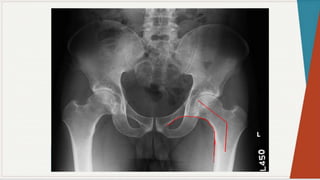

Radiografia Simples:

◗ Incidência ântero-posterior:

observar

as

características: espaços

articulares e

linhas

seguint

es

pélvica

s,

presença de qualquer doença óssea, ângulo colo-

diafisário, forma da cabeça femoral, presença de

osteófitos, evidência de fratura ou luxação,

evidência de deformação pélvica.